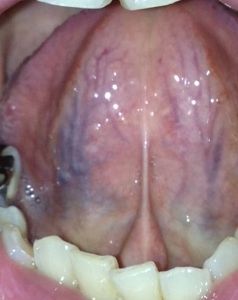

¡Ú2014ǯ7·î30Æü´ÁÊýÌôÉþÍÑ287Æü¸å¤ÎÀå¤Îɽ¡Û

¡Ú2014ǯ7·î30Æü´ÁÊýÌôÉþÍÑ287Æü¸å¤ÎÀå¤Î΢¡Û